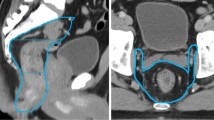

Figure 1 shows IMPT dose distributions from the original plan computed on the pCT and rpCT as well as the vCT-adapted plan on the rpCT (labelled rpCTadapt) and on the vCT (labelled vCTadapt) for two representative patients. Over-dosed regions in the low dose PTV were observed on the rpCT in the vicinity of the high dose PTV and the skin when applying the original plan for Pat2. This over-dosage was reduced by adapting the plan using the vCT. For Pat5 over-dosage was observed (up to 109 % of the high dose PTV prescription dose, which corresponds to about 120 % of the low dose PTV prescription dose) in the high dose PTV and could be eliminated in the adapted plan. In both cases, dose distributions of the adapted plan on the vCT were found similar to the original planning scenario (pCT).

Dose distributions for Pat2 and Pat5 from the original plan on the pCT and rpCT as well as the adapted dose distributions on the rpCT (rpCTadapt) and vCT (vCTadapt). The high and low dose PTVs are indicated in blue and green respectively. The spinal cord PRV is also shown. For the high dose PTV, the 95 % dose level corresponds to 105 % on the color bar, which is relative to the low dose PTV prescription. Hot spots correspond to 120 % or more of the low dose PTV prescription